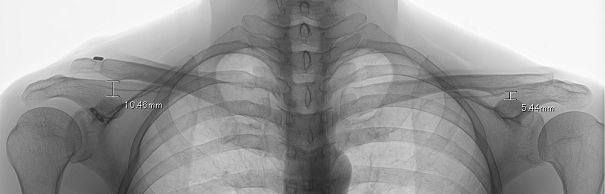

烏口鎖骨靭帯再建術を施行して10年経過した方ですがこの方は手術後右肩の肩鎖関節の転位(ずれ)がみられます。そのずれは手術前ほどのずれではありません。